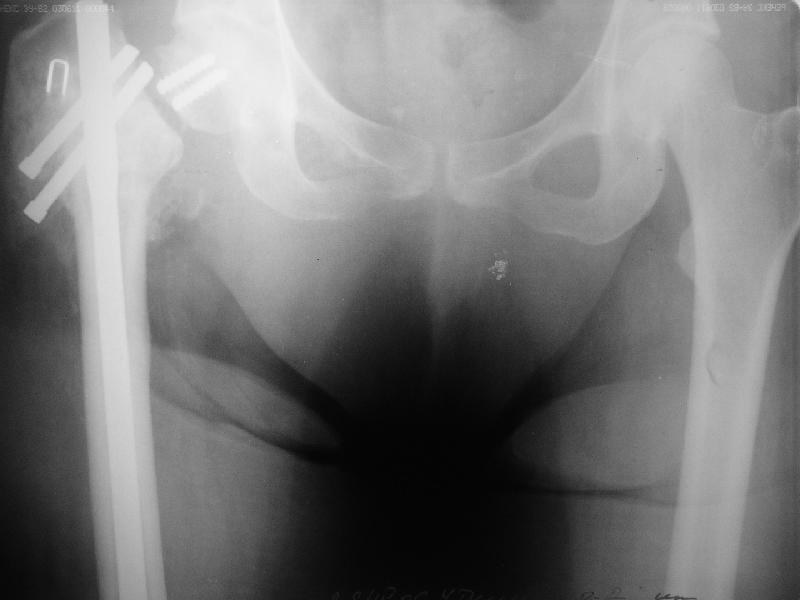

Уважаемые коллеги, хотелось бы услышать ваше мнение по следующему случаю: Относительно молодая женщина(39 лет), поступила в клинику в марте 2005 года, через 3 месяца после травмы с Неправильно срастающимся поперечным межвертельным переломом правого бедра. Был выполнен закрытый интрамедуллярный остеосинтез правого бедра канальным реконструкционным стержнем ChM. Ожидали бОльших проблем на операции, результату обрадовались. Как оказалось, зря. Сращение наступило через 3,5 месяца после операции. В ноябре 2005 года произошел перелом шейки бедра и винтов в ней. В апреле 2006 импланты были удалены. В приложении фото и рентгенограммы больной. Сопутствует ожирение 4 ст. (при росте 168 см., вес больной 140кг.), сахарный диабет II тип. Имеется медиальная неустойчивость коленного и голеностопного суставов, при нагрузке колено вальгируется на 15-20 градусов. Вопросы: 1.Целесообразность эндопротезирования (в настоящий момент передвигается на ходунках)? 2.Если ответ на первый вопрос-да, то каким протезом? 3. С какими проблемами можем столкнуться во время и после операции? Заранее благодарен за ответы. Салават Салаватов, Екатеринбург

Если осознанный выбор пациентки на лечение, то протезирование т\б сустава не таит в себе огромных сложностей - только глубина операционной раны и рубцово измененные ткани. Учитывая проксимальный дефект бедренной кости предпочтительна ревизионная ножка ZMR ZIMMER. Чашка любая безцементная.

Медиальная нестабильность коленного сустава скорее всего результат COXA vara. Что тут только МCL или имеются костые разрушения? От этого зависит тактика дальнейшего лечения. Различные наружные корректоры, фиксаторы на такой конечности бесполезны. для голеностопного сустава вполне достаточно орт. обуви.